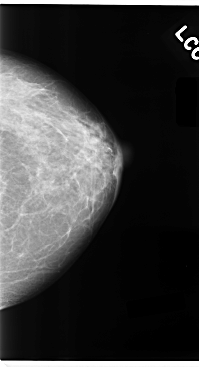

C_0100_1.LEFT_CC

LEFT_CC LINES 4760 PIXELS_PER_LINE 2576 BITS_PER_PIXEL 12 RESOLUTION 50 NON_OVERLAY